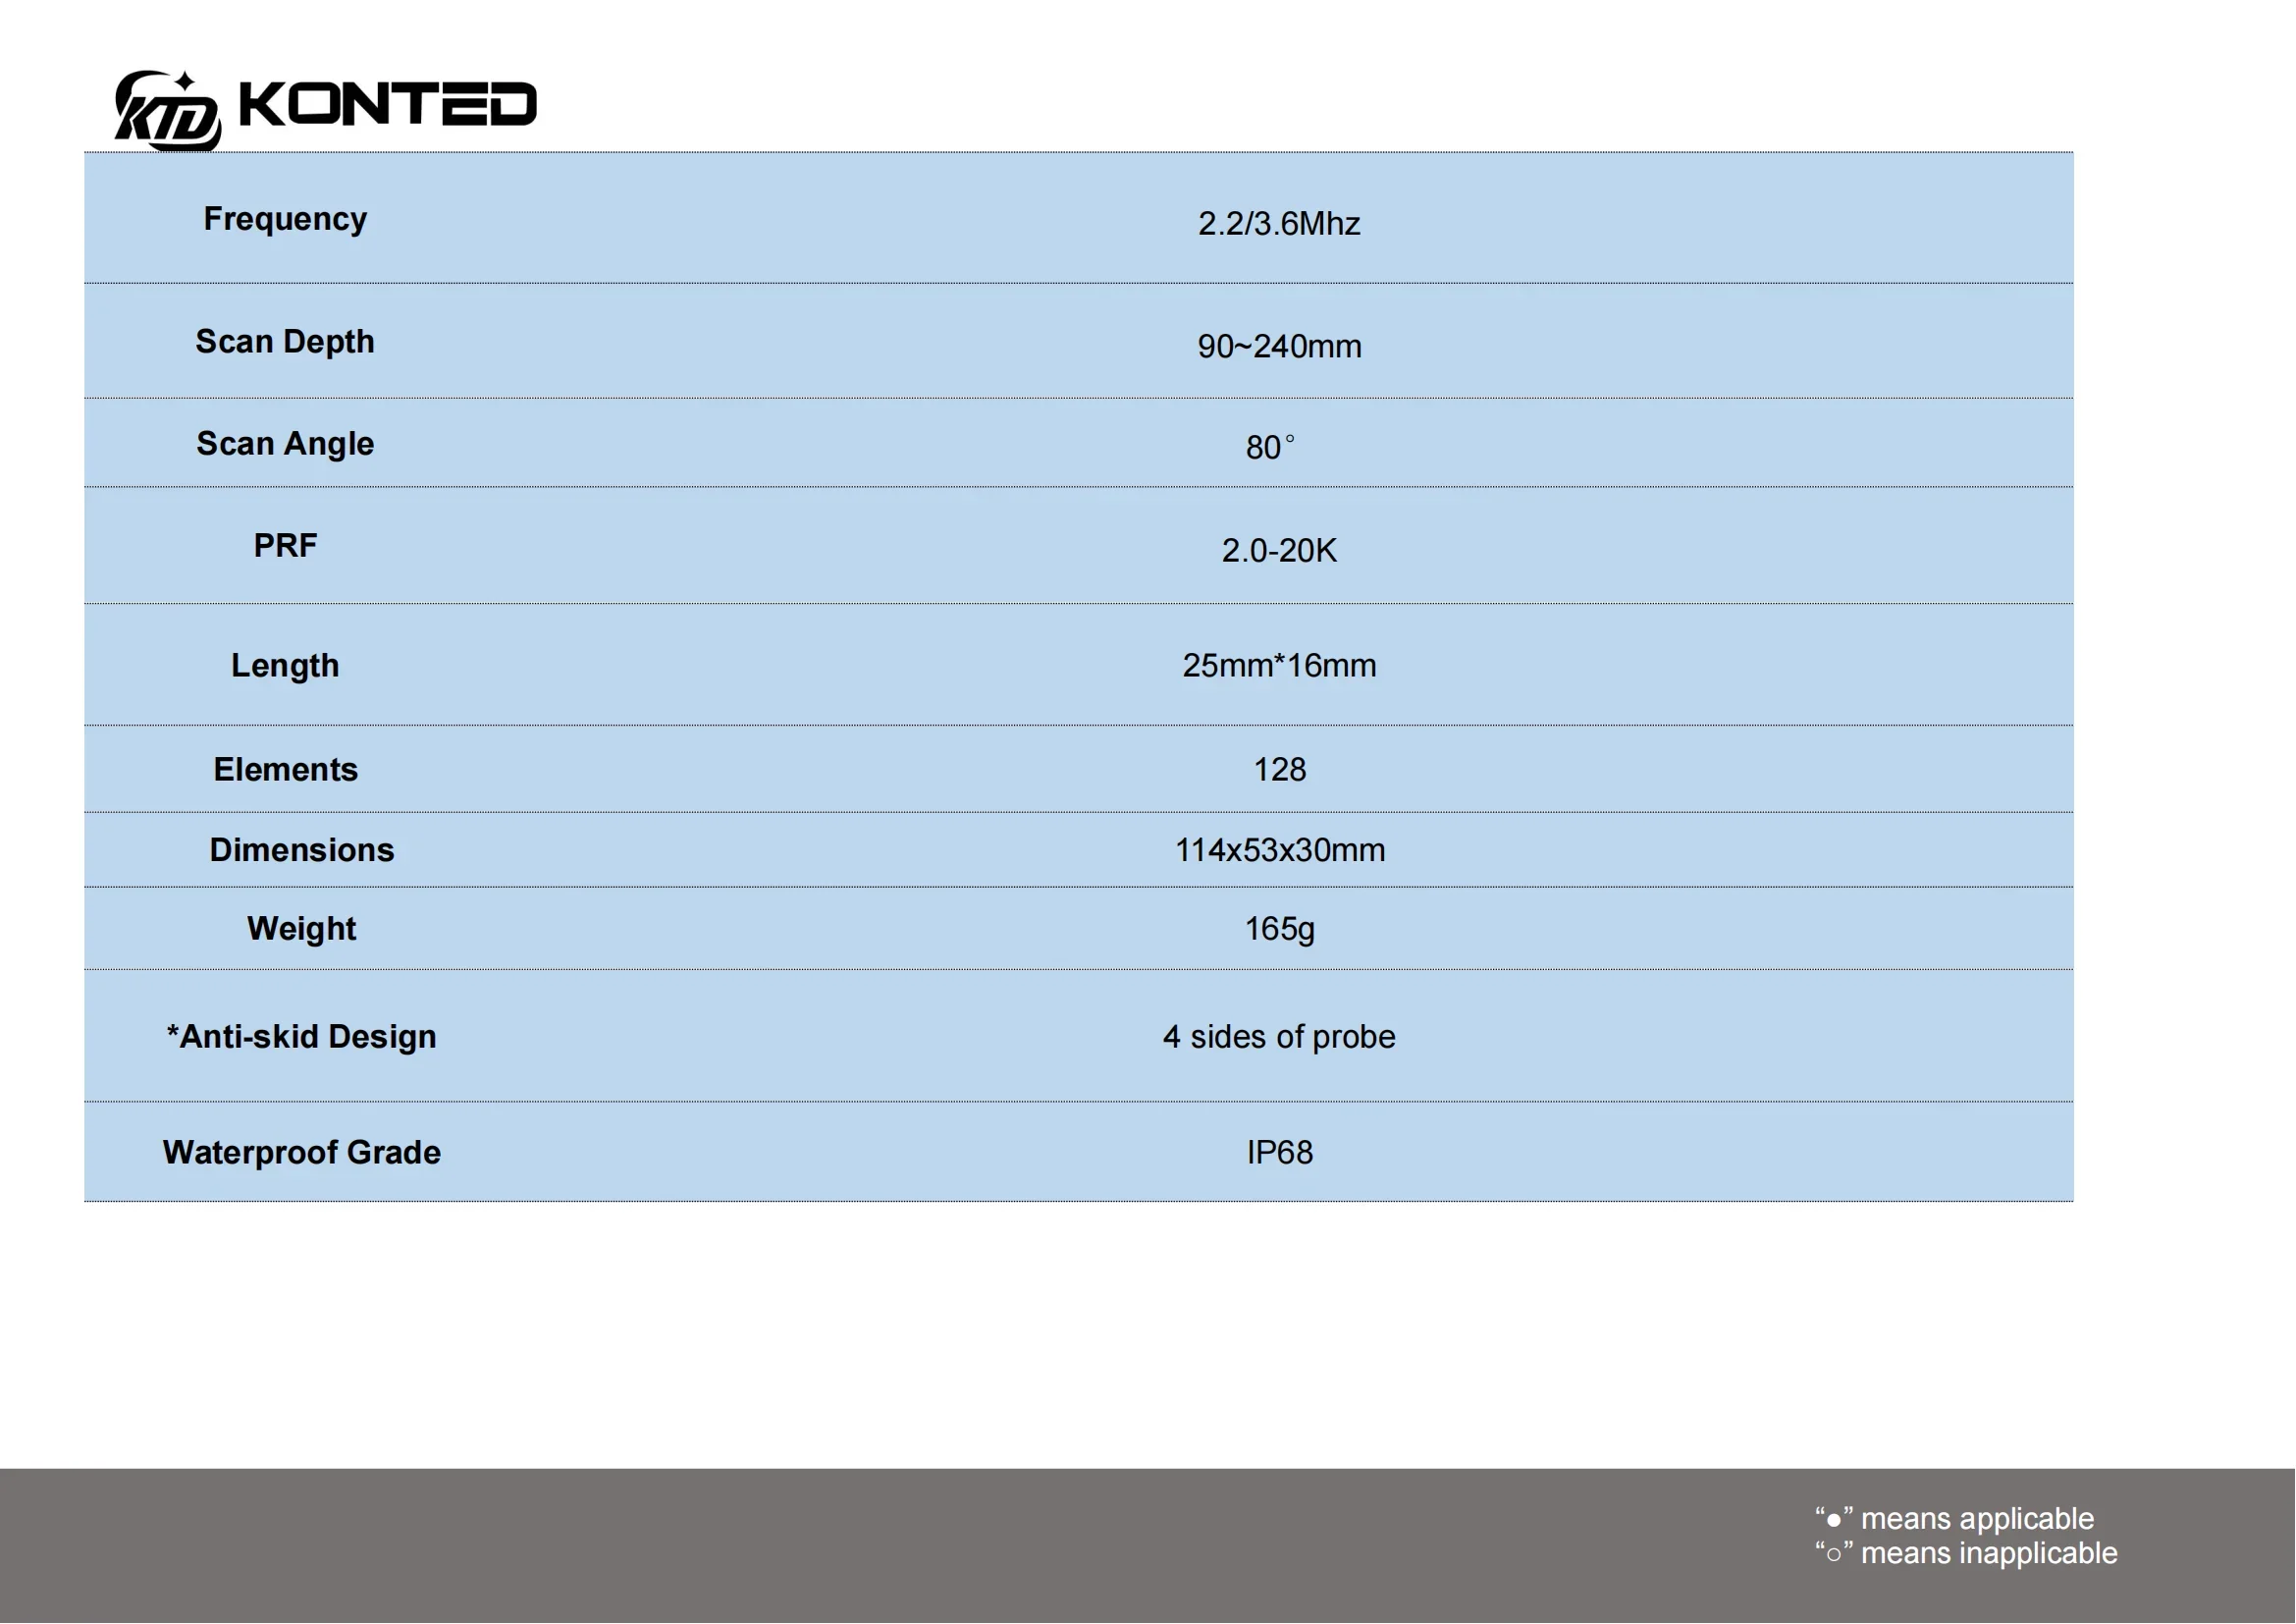

Convex Probe Parameters

-Scanning system: array sweep

-Frequency: 3.5MHz

-Probe element: 80

-Depth: 90-200mm

-Field of view: 80 degree

-Display mode: B,BM

-Image gray scale: 256 level

-Gain:30-105Db

-Measure: distance, area, obstetrics and other

GA(CRL),GA(BPD),GA(GS),GA(FL),GA(HC),GA(AC)

-Language: English, Russian, Italian, Spanish, Chinese, Portuguese

-Power: by built-in battery

-Power consumption: 10W (probe run) /2W (probe stop)

-Battery last: 3 hours

-Footprint: 156mmx60mmx24mm

-Weight: 308 g

Convex Probe Pictures: